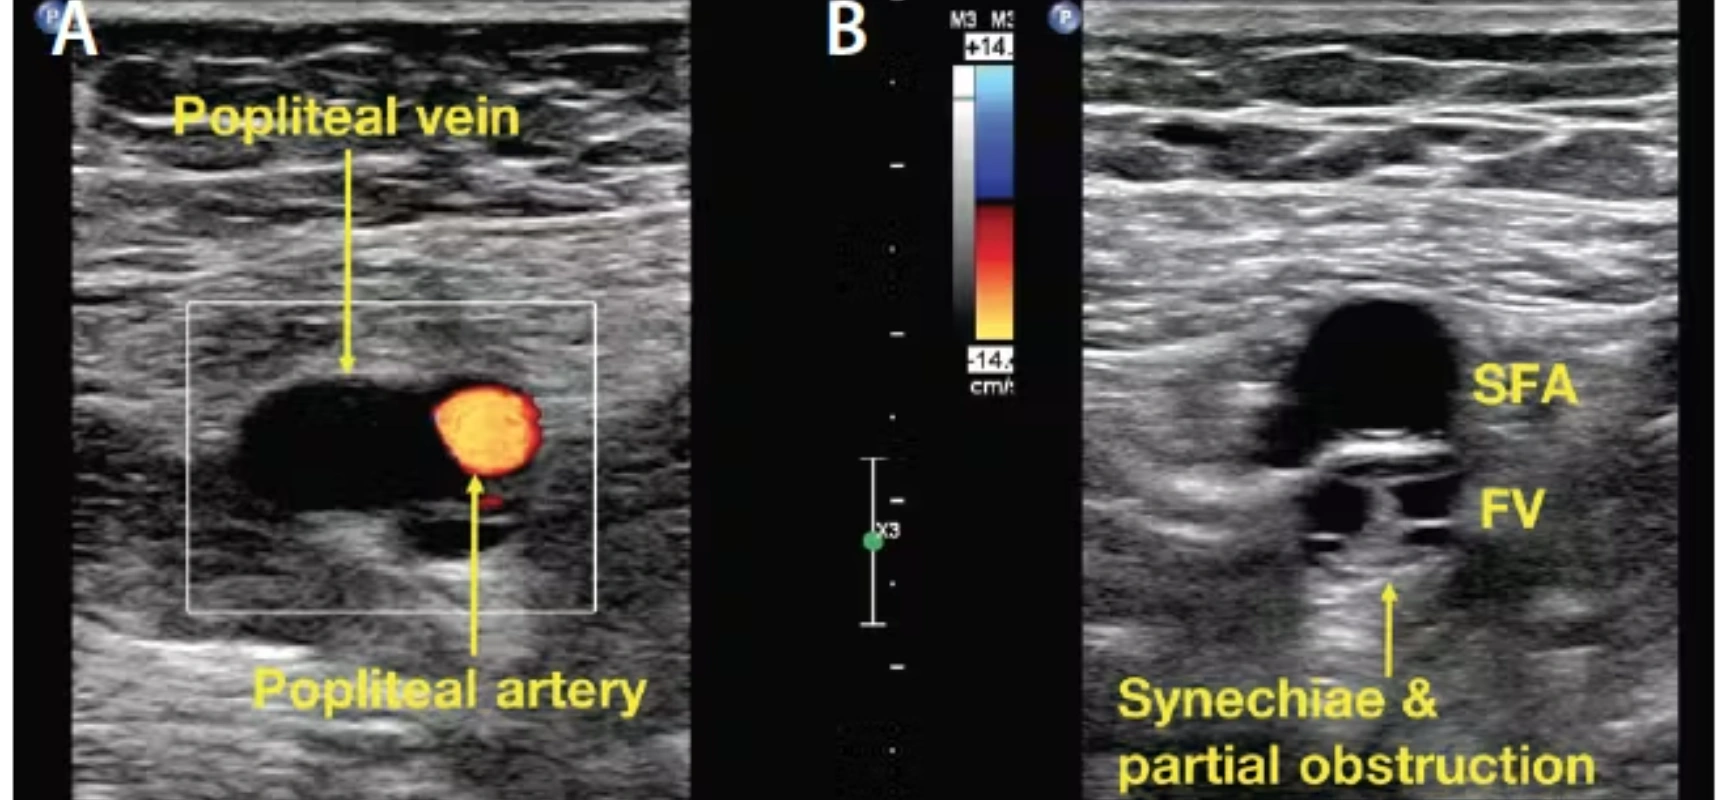

Duplex Color Doppler is an advanced ultrasound technique that evaluates blood flow in arteries and veins while simultaneously visualizing vessel structure. It combines traditional B-mode imaging with Doppler flow analysis to detect blockages, clots, narrowing, and vascular abnormalities.

Color Doppler visualizes direction and velocity of blood flow.